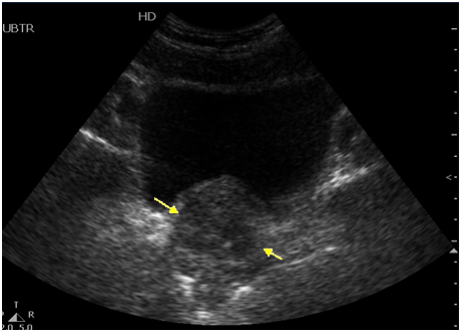

66. 病人因上腹部不適,接受超音波檢查,下圖中箭號所示,最可能為何種病灶?

(A)血管瘤 (B)囊腫 (C)圓韌帶 (D)結石